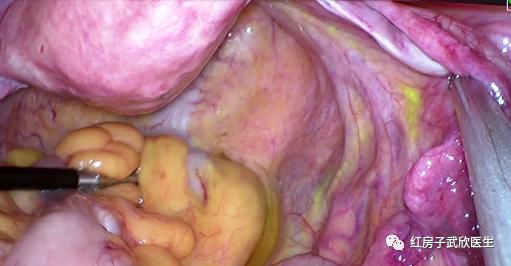

2018年3月19日对小叶来说是一个永生难忘的一天,她再一次进入了手术室,这一次她不再孤独和害怕,因为她相信武教授能够帮她实现愿望!在全麻后,武教授帮她行了宫腔镜检查+宫颈管局部切除术+腹腔镜下前哨淋巴结活检+大网膜部分切除术+腹膜多点活检术。宫腔镜下:宫颈管2点处仅见毛糙面,子宫壁内膜均匀。电切镜于宫颈内口水平1点至3点瓣状切除颈管内壁。腹腔镜下,在吲哚菁绿的指引下切除了前哨淋巴结送活检。